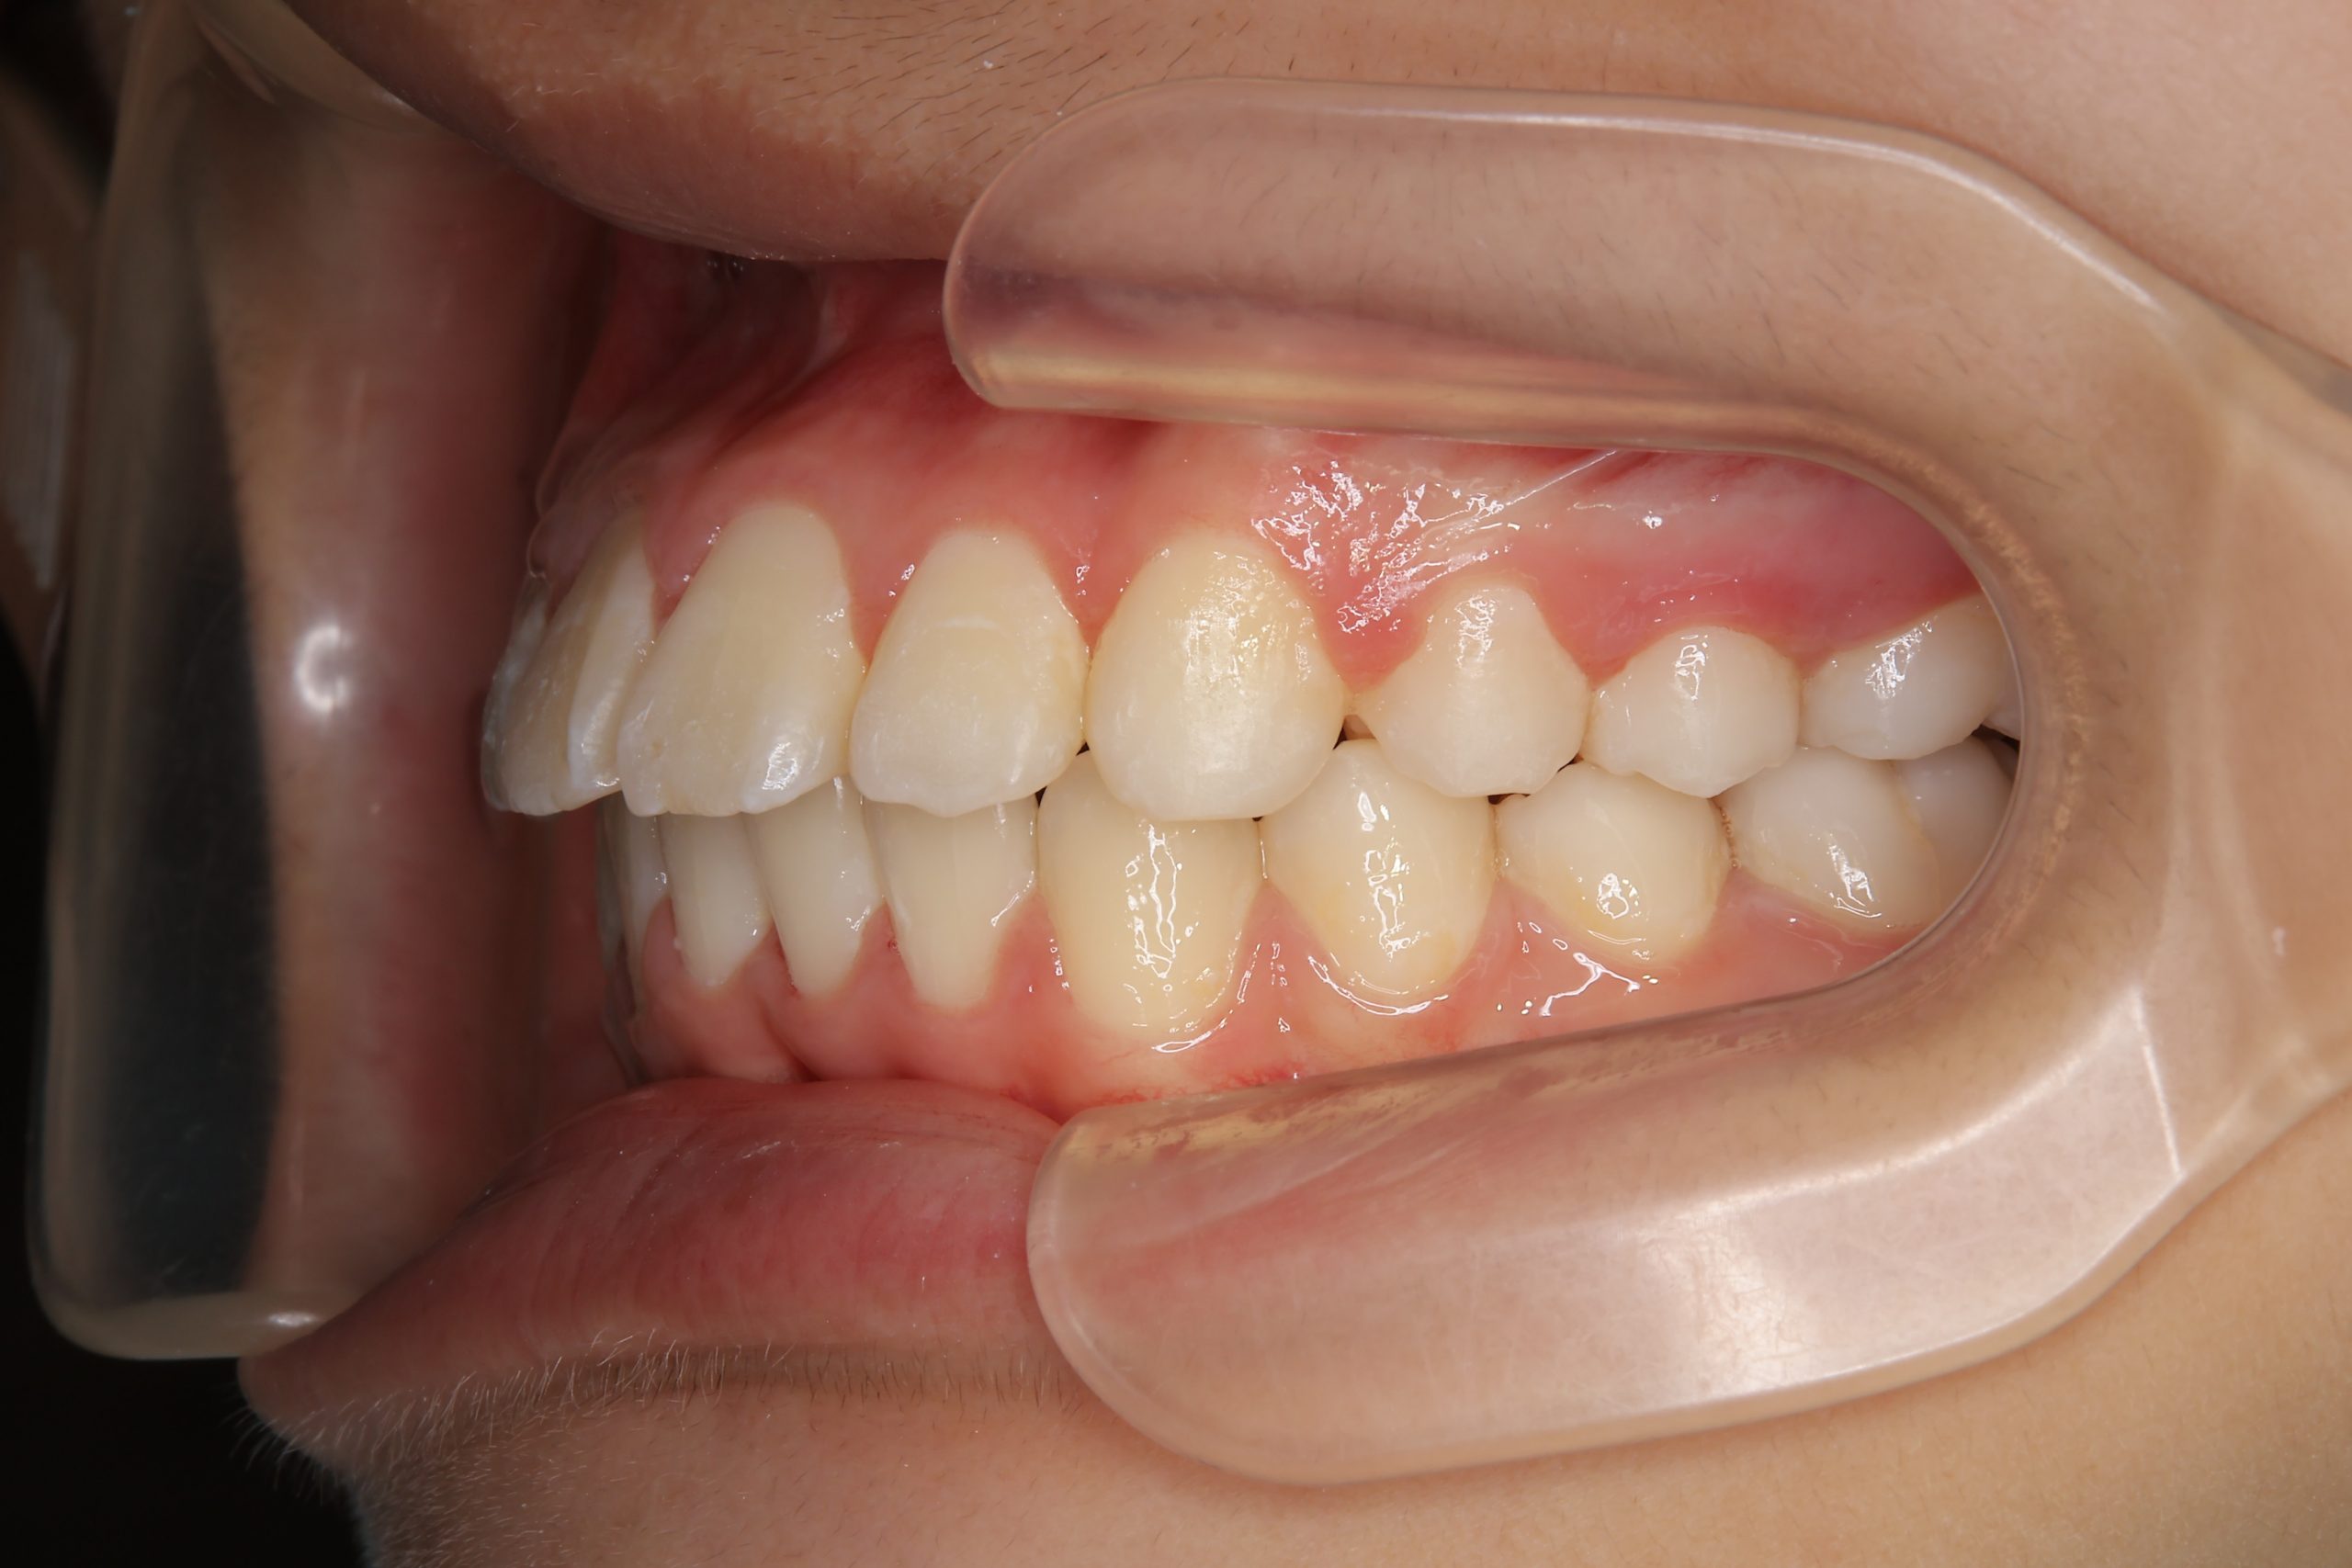

アフター

ワイヤー矯正治療|症例_1324

施術内容 MSEと下顎リンガルアーチを用いて上下顎骨を拡大した。

その後マルチブラケット装置を用いて非抜歯で歯牙を配列し、良好な咬合を獲得した。

治癒期間 1年5か月間